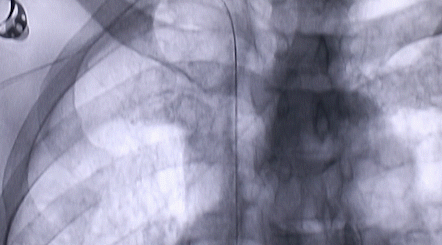

1月12日,西安國際醫(yī)學中心醫(yī)院心臟外科郭穎強主任團隊成功為一名腹主動脈閉塞、右側腎動脈閉塞、左側腎動脈重度狹窄、腹壁淺表動脈側支循環(huán)形成、高血壓病3級(極高危組)合并閉塞性周圍動脈粥樣硬化、急性腎功能不全的老年患者實施腎動脈球囊擴張 腎動脈支架植入術 動脈血栓抽吸術 髂動脈開通術,治好了困擾患者多年的頑固性高血壓?;颊吣壳翱祻土己?,將于近日出院。

按照術前制定的方案,郭穎強主任和楊金保博士首先嘗試開通閉塞的右腎動脈,但由于血栓機化、鈣化嚴重,右腎動脈難以開通。遂謹慎擴張狹窄的左腎動脈,并成功植入一枚支架。之后經過反復旋磨、抽吸,順利開通髂動脈,但腹主動脈閉塞段仍難以擴通。此時,患者居高不下的血壓很快恢復到正常水平。